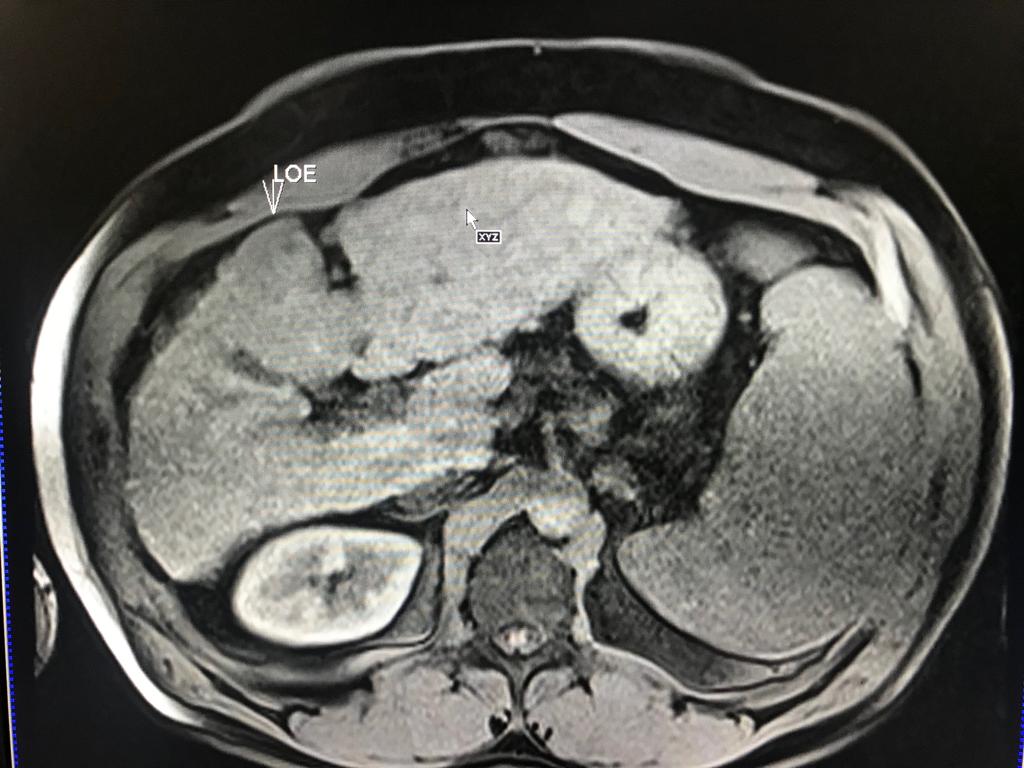

En este contexto, toda nodulación mayor de 1 cm, debe ser evaluada idealmente con RM trifásica con secuencia de Difusión , para discriminar si se trata de nódulos de regeneración , nódulos displásicos o hepatocarcinoma.

En el presente caso, encontramos una lesión típica de hepatocarcinoma en el segmento 5 ( hiperintensa en T2, restringe en la Difusión con ADC bajo. Realza heterogéneamente postcontraste EV, con wash out y presencia cápsula tardía).

El objetivo es identificar dentro de la multifocalidad de nódulos , un hepatocarcinoma precoz o de pequeño tamaño , cuando la posibilidad de tratamiento con intención curativa es viable , a pesar de la cirrosis.